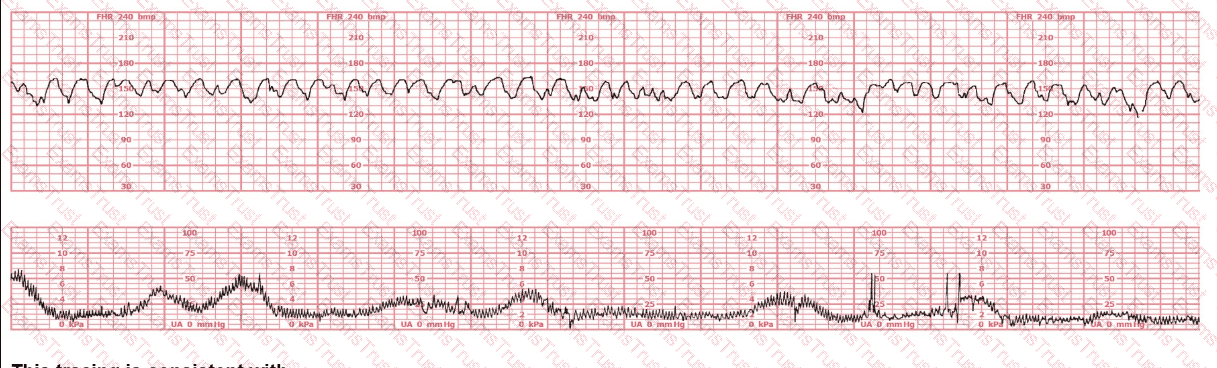

A woman has been 5 cm dilated for the past 3 hours. The tracing shown has developed over the last 30 minutes. The best initial course of action is to: